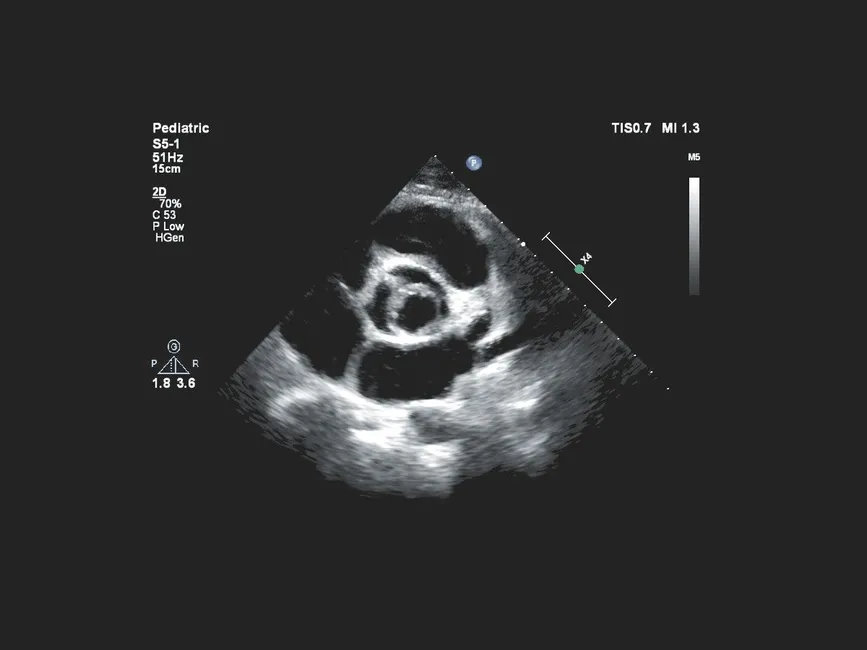

Philips Affiniti 70 построена на архитектуре старшей линейки EPIQ и ориентирована на отделения, где требуется экспертный уровень визуализации при высоком потоке пациентов. Система обеспечивает стабильное качество изображения на сложных пациентах за счет технологий подавления шумов и пространственной компаундной визуализации, поддерживает расширенные допплеровские режимы и автоматизацию измерений для сердечно-сосудистых исследований. Наличие средств объемной визуализации и эластографии делает аппарат универсальным инструментом для комплексной оценки органов и сосудов, в том числе при онкологических и интервенционных задачах. При этом интерфейс управления и логика пресетов оптимизированы для сокращения времени на настройку исследования и снижения нагрузки на врача.

| Расширенные кардиопакеты | Специализированные пресеты и измерения для эхокардиографии, включая оценку функций камер и клапанов (опционально). |

- Кардиология: оценка структуры и функции сердца у взрослых и детей (при наличии соответствующих пакетов).